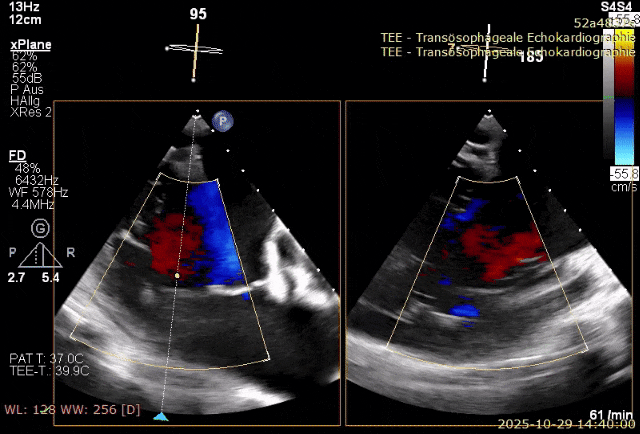

术前超声提示:三尖瓣反流为torrential

术后即刻超声与DSA结果显示:人工瓣膜定位准确,术前为瀑布样反流,术后仅残存微量瓣周漏,未发生围手术期并发症。整体手术过程顺利,达到了预期治疗目标。

术后超声提示反流消失